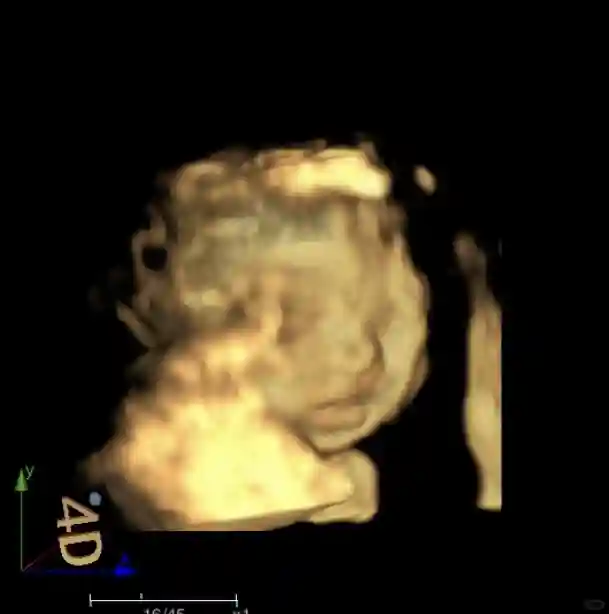

24W+4 大排畸心超险过+喜提球拍状胎盘

我的小汤圆很调皮,大排畸做了三次才过,因为糖耐没过喜提小糖人了,但还是为了让宝宝配合,吃了巨多巧克力,果然我的宝宝喜欢吃甜食,吃了很多巧克力后的第三次终于过了,不过喜提球拍状胎盘,之前就看到过类似情况,属于非正常胎盘,这个概率也被我遇到,简直了,就是后期可能会影响宝宝吸收,朱主任也说了,以后关注胎儿的发育情况就行,还有一个就是顺产比较凶险,反正本来就是打算剖的,也无所谓了。

心超宝宝很给力,一次就过,大概十分钟的样子,这关过了我真是放心不少。